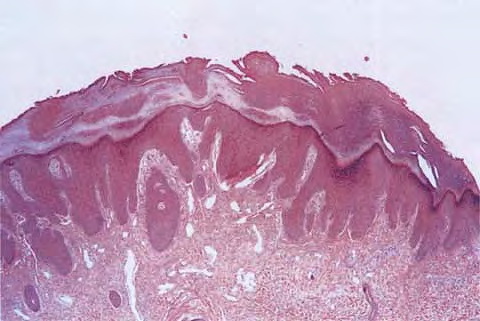

Prurigo nodularis =الاكال العقيدي